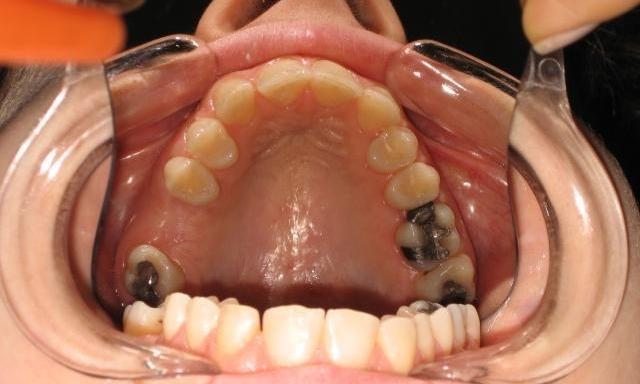

Before